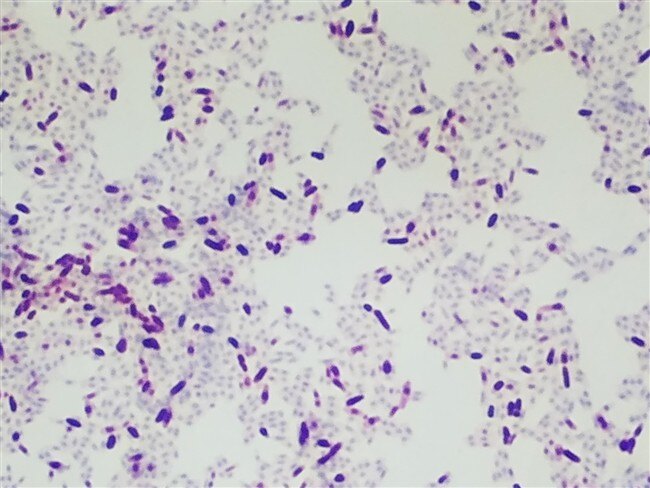

Acid Fast stain – Ziehl Neelsen

Acid-fast organisms are typically found when looking for things like tuberculosis and other respirat...